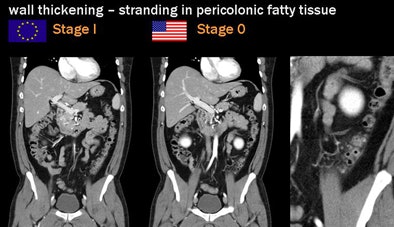

Two staging methods are in widespread use: the Hanson/Stock staging method popular in Europe and the modified Hinchey (Wasvary) technique dominant in the U.S., Rogalla said.

![]() |

| Two staging methods are in widespread use: the Hanson/Stock staging method popular in Europe and the modified Hinchey dominant in the U.S. All images courtesy of Dr. Patrick Rogalla. |

Per the Hinchey method, for example, complicated disease is classified as stage I as long as the complication is local, he said. Once an abscess is found at CT, patients are potential candidates for CT-guided catheter placement under fluoroscopy to drain the abscess.

| Diverticular disease above reveals wall thickening and stranding in the pericolonic fatty tissue at CT. Case below shows moderate obstruction and acute inflammation. Both are classified as stage 0 by the Hanson/Stock method and as stage I by the modified Hinchey method. |